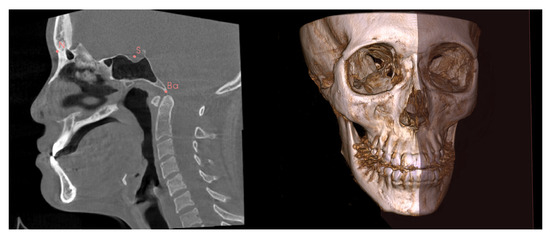

| H0 | Point corresponding to the Gonion point on the deviated side. |

| H1 | Point located on the external cortical bone of the mandible, on the same coronal slice as H0, and 10 mm above H0 on the axial slice. |

| H2 | Point located on the external cortical bone of the mandible, on the same coronal slice as H0, and 10 mm above H1 on the axial slice. |

| H3 | Point located on the external cortical bone of the mandible, on the same coronal slice as H0, and 10 mm above H2 on the axial slice. |

| H4 | Point located on the external cortical bone of the mandible, on the same axial slice as H0, and 10 mm anterior to H0 on the coronal slice. |

| H5 | Point located on the external cortical bone of the mandible, on the same coronal slice as H4, and 10 mm above H4 on the axial slice. |

| H6 | Point located on the external cortical bone of the mandible, on the same coronal slice as H4, and 10 mm above H5 on the axial slice. |

| H7 | Point located on the external cortical bone of the mandible, on the same coronal slice as H4, and 10 mm above H6 on the axial slice. |

| H8 | Point located on the external cortical bone of the mandible, on the same axial slice as H4, and 10 mm anterior to H4 on the coronal slice. |

| H9 | Point located on the external cortical bone of the mandible, on the same coronal slice as H8, and 10 mm above H8 on the axial slice. |

| H10 | Point located on the external cortical bone of the mandible, on the same coronal slice as H8, and 10 mm above H9 on the axial slice. |

| S0–S10 | Extension of hard tissue point (H0 to H10) perpendicularly from the MSP to the outermost soft tissue contour of the face. |

| H’0–H’10 | Hard tissue points on the non-deviated side of the mandible, corresponding to H0 to H10. |

| S’0–S’10 | Soft tissue points on the non-deviated side, corresponding to S0 to S10. |

| Hard tissue prominence (mm) | The perpendicular distance from a hard tissue point to the MSP. |

| Soft tissue prominence (mm) | The perpendicular distance from a soft tissue point to the MSP. |

| Soft tissue thickness (mm) | The distance between a hard tissue point and a soft tissue point perpendicular to the MSP. |

| Menton deviation (mm) | The perpendicular distance from the menton point to the mid-sagittal plane. |